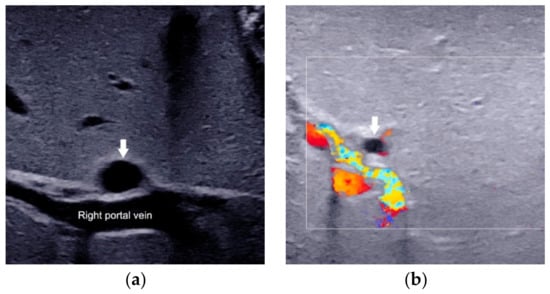

| Triangular cord sign | The thickness of the echogenic anterior wall of the right portal vein, with or without HA. | >2.0 mm not including HA, or >4.0 mm including HA | ≤2.0 mm not including HA, or ≤4.0 mm including HA | Strongly suggest BA |